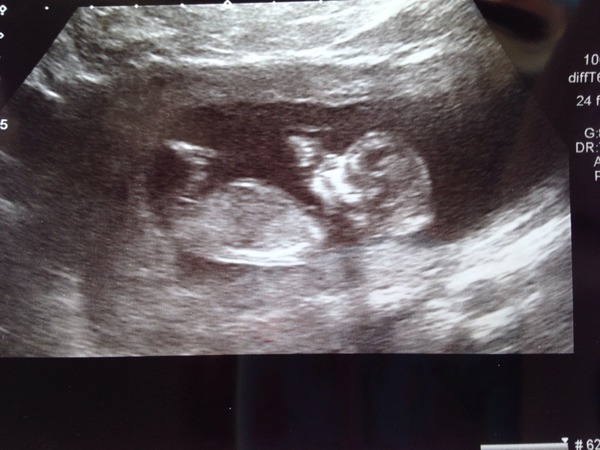

So here is the next heir to the throne :)

All ok except the little bugger absolutely refused to get in the right position for the nt test, no matter what I did. So it's back for more bloods in a couple of weeks.

Aw heir! Amazing, isn't it? Was there much wriggling going on? I'm convinced in my 20 w scan with ds that he was smiling. Smile

A little bit but it was mostly lazy like its daddy!

Hee hee! They say try having a fizzy drink or some chocolate before a scan to encourage them to get moving! You'll have to try it at the next scan. :) x

Heir lovely pic.

Lovely piccy heir sorry you're needing to go back for the other part of the test but at least you can see you little one again so soon.

Heir your pic is amazing! You don't want them wiggling too much at the 20w scan or you won't get to find out if you're team pink or blue! Does everyone want to know or do some here like surprises?